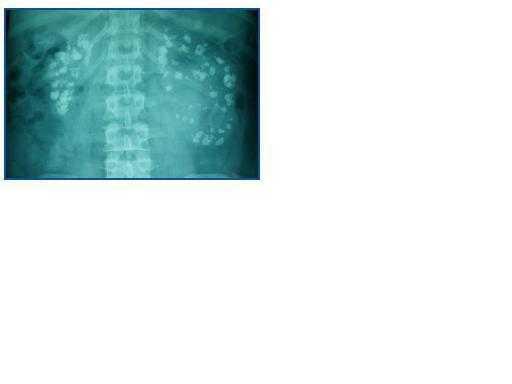

Apartir de los 16 años de edad, inicia un deterioro lento pero progresivo de la función renal, con un empeoramiento de la nefrocalcinosis (figura 1). A los 19 años de edad, se detecta pérdida de audición y se le diagnostica sordera neurosensorial bilateral, precisando audífono.

En las últimas revisiones se constata un aumento progresivo de la nefrocalcinosis, y de forma paralela existe un aumento progresivo de Hb y Htco con poliglobulia actual (tabla 1) y nivel de EPO normal (11,6 mU/ml).

Figura 1.